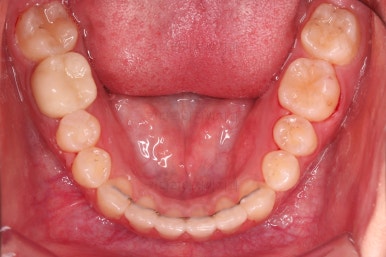

마찬가지로 초진 시 입안의 모습인데요.

위아래 앞니가 삐뚤고, 송곳니는 덧니처럼 불룩 튀어나가 있네요.

위아래 앞니는 안으로 굽어 들어와 있는 옥니(뻐드렁니 반대) 양상이었고요.

그리고 마무리 때 디테일에 문제가 생길 수 있는 부분인데, 윗니 대문니(가장 중간 치아)와 송곳니 사이의 치아를 작은 앞니라고 하는데요.

이 작은 앞니가 가져야 될 크기보다 더 작은 양상이었습니다.

이런 치아를 왜소치라교 표현합니다.